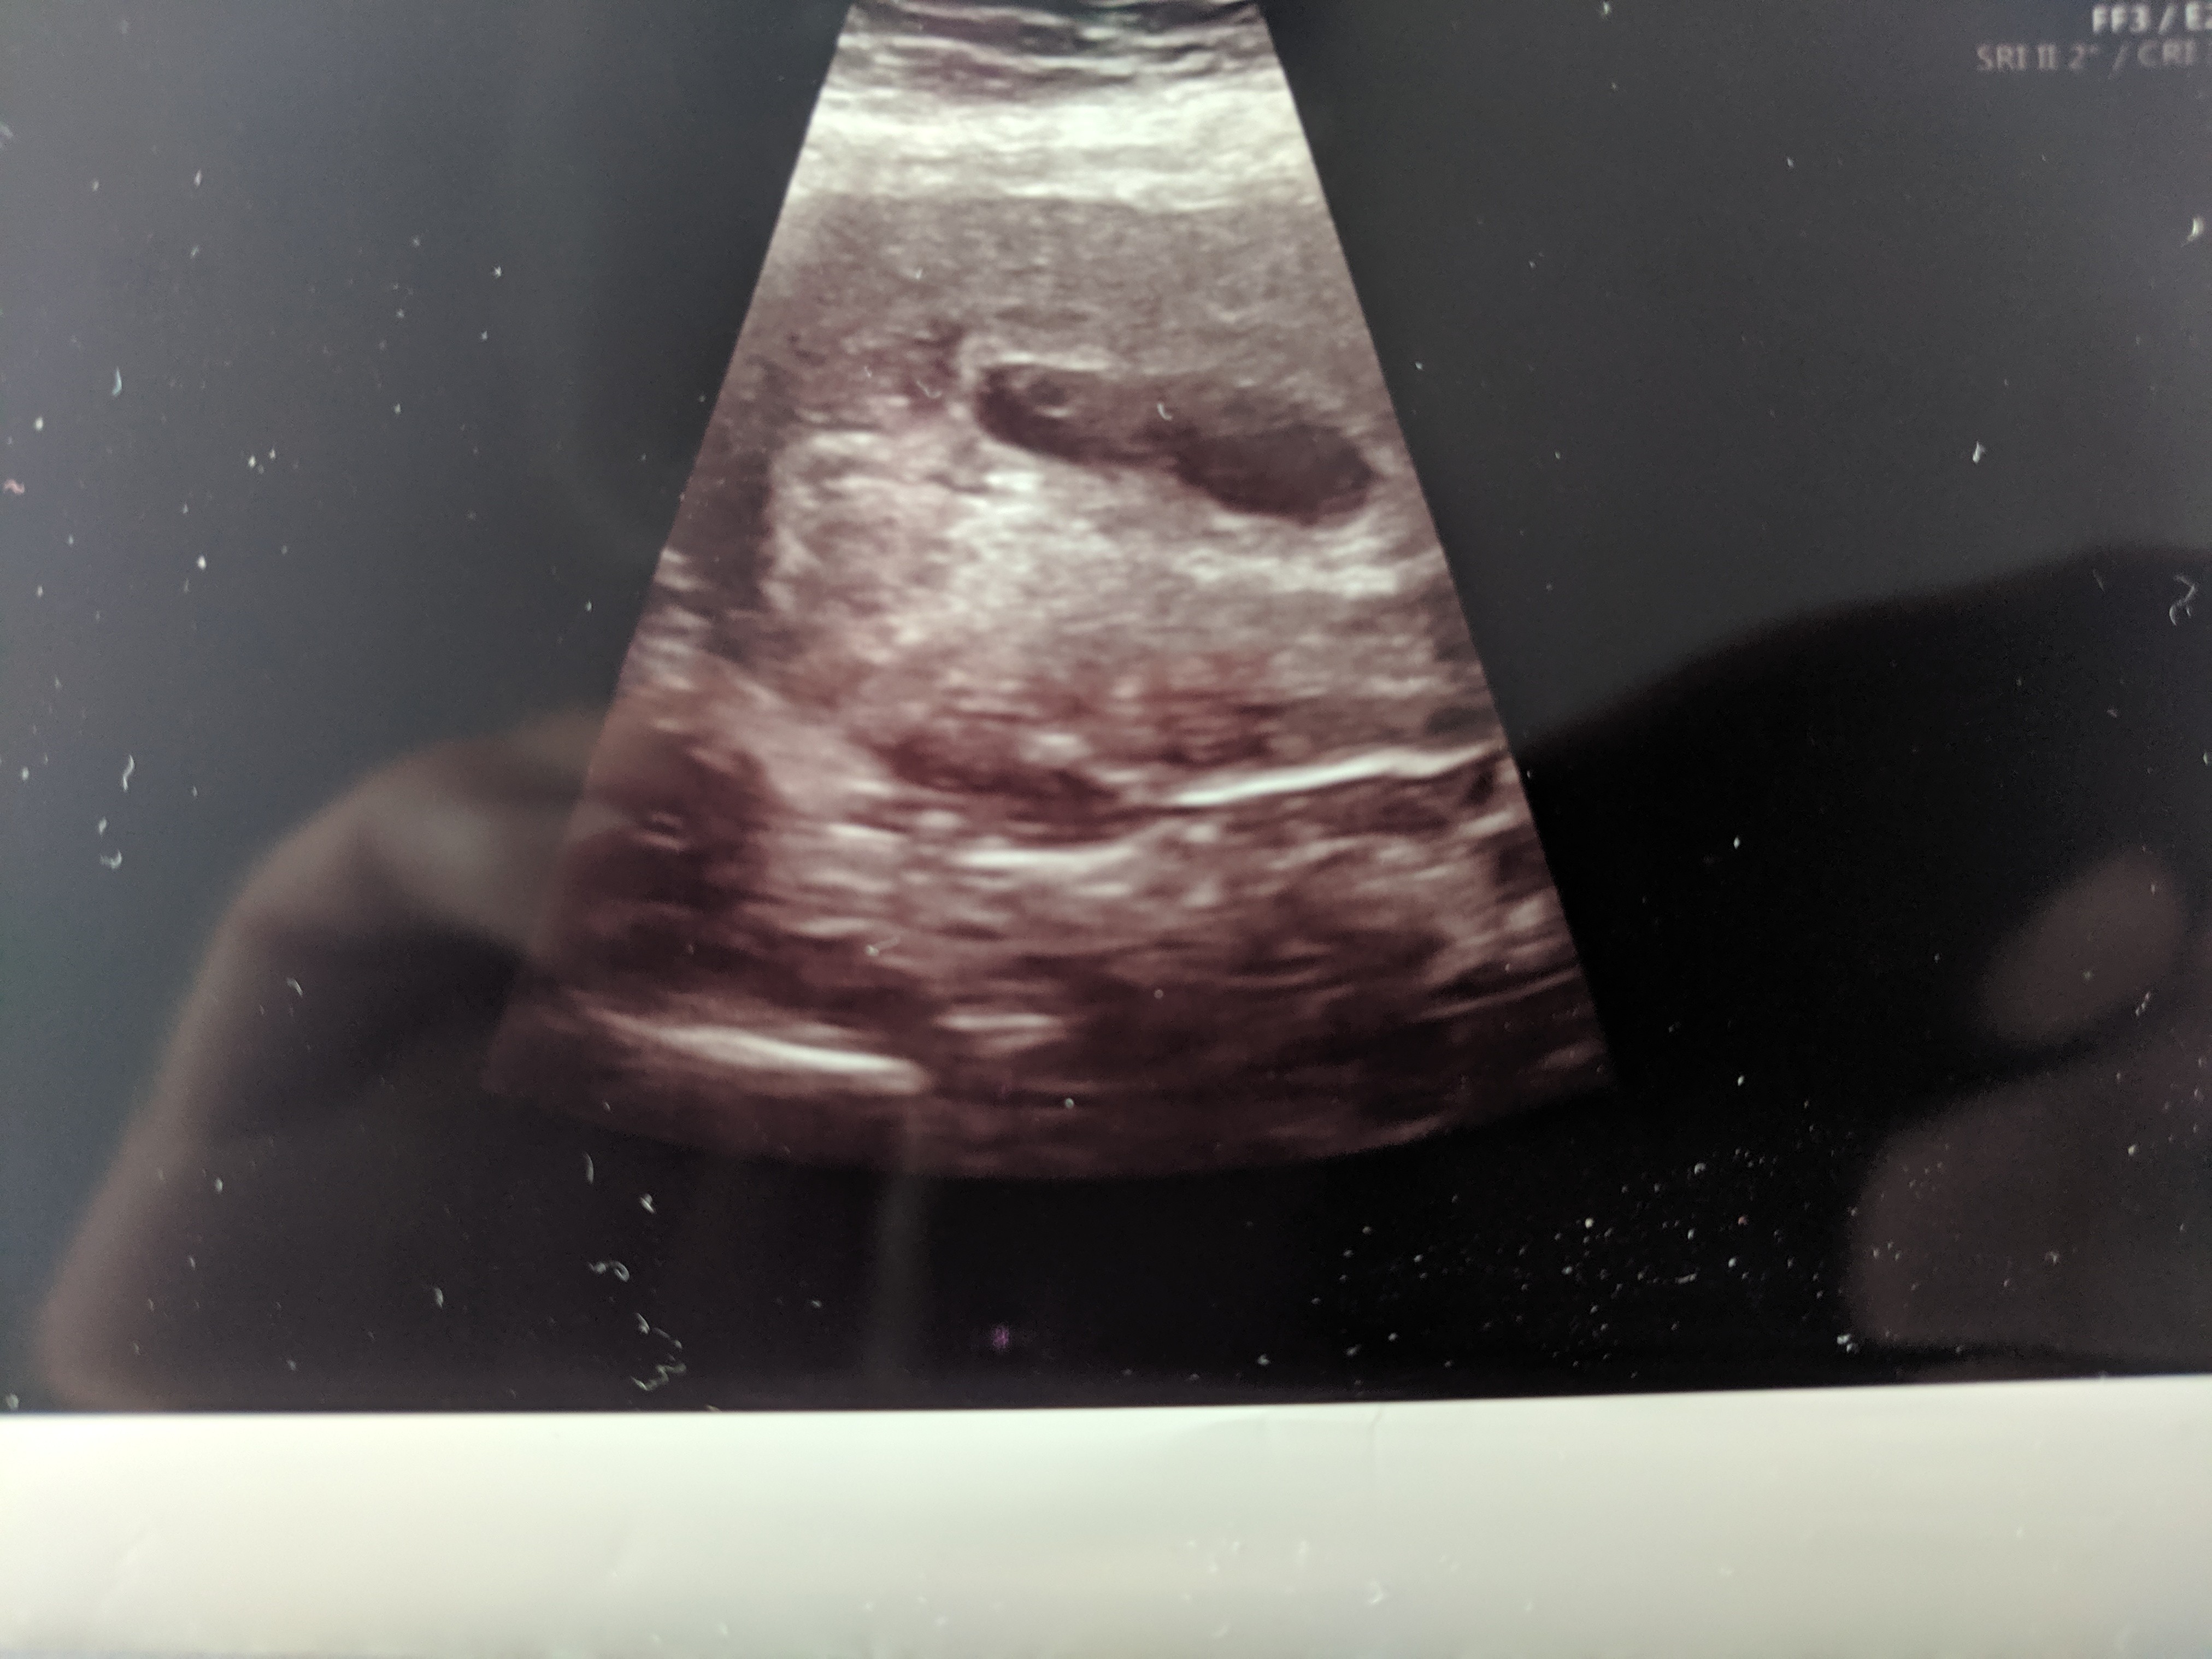

Czy widać tu zarodek, czy to pusty pęcherzyk ?

Dziewczyny, pisałam już na innym wątku, ale słaby jest odzew. Zdjęcie USG z 7t2d z terminu ostatniej miesiączki. Ale UWAGA - zdjęcie robione z USG przez powłoki brzuszne. Dopochwowym USG nic nie było widać, bo mam tyłozgięcie macicy. Widzicie tu zarodek, czy to raczej puste jajo ....?

Powiedział coś takiego " w ciąży pani jest ale wygląda to na wcześniejszy tydzień niż wychodzi z ostatniej miesiączki " a ja w szoku nie dopytalam, czy jest zarodek. Dał skierowanie na betahcg, wyszło najpierw ok 41700 a za 48 godz 45500.

Sprzęt jest ok, po prostu USG było robione przez brzuch, bo dopochwowo ze względu na moje tyłozgięcie nie było nic widać... A USG przez brzuch robione przed 13 tyg jest niedokładne ( tak czytałam)